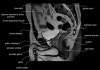

엉덩이 관절(고관절)의 MRI 단면 영상

- Checklist

1) Femur : Osteonecrosis, Fracture or Edema

2) Cartilage surface : Fissure, Fraying, Thinning or Defect

3) Joint recess : Chondral debris or Corpora aliena

4) Labrum : Tear, Detachment, Fraying or Degeneration

5) Acetabulum : Shallow contour?

6) Muscle and tendon : Tear or Strain

7) Trochanteric or Iliopsoas bursitis?

8) Check the symphysis pubis, superior/inferior pubic rami, ilium, sacroiliac joint and sacrum on large FOV coronal images